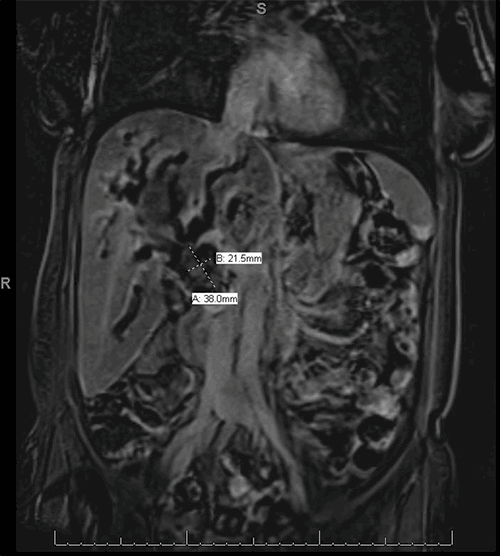

A CT scan of her abdomen was performed showing a 7.5 cm lesion in the right hepatic lobe with intrahepatic biliary ductal dilation and irregular beaded appearance. MRI was then performed showing a large complex lobulated mass in the right hepatic lobe measuring 9.7 cm and biliary obstruction due to mass effect and compression of the porta hepatis (Figure 1).

Figure 1. MRI of abdomen and pelvis showing a 2 x 3 cm mass at the hepatic hilum and surrounded by an 8 x 12 cm hematoma. Coronal (SUB_COR Post) view.